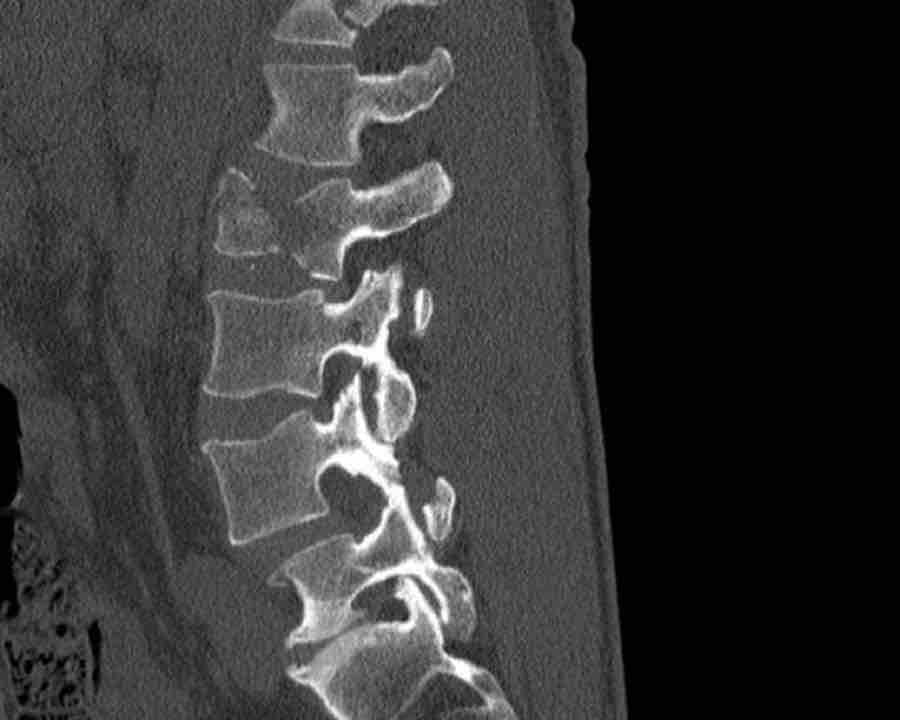

Scroll through images.

What is the highest AO-level?

Findings

- No dislocation ( no C type).

- Mainly horizontal fractures of spinous processus at multiple levels (B-type).

- Split fracture L2 (type A2).

Conclusion

Injury type B2 + A2 at level L2.